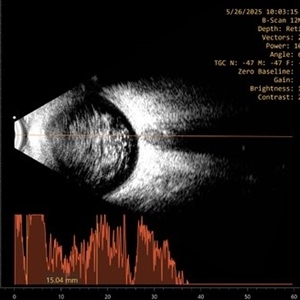

Ultrasound B-scan image of 63 year-old gentleman with extensive asteroid hyalosis. The bodies stain metachromatically and exhibit birefringence. It appears as discrete, highly echogenic, spherical or star-shaped foci in the vitreous chamber without posterior acoustic shadowing.

Photographer: Dr Moazzam Parvez, Netralayalam, Kolkata

Imaging device: Appaswamy B Scan

Condition/keywords: asteroid hyalosis, birefringence, ul